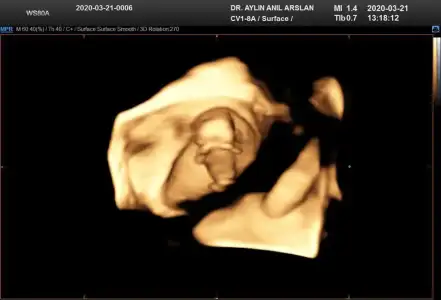

11+3 ama cok net değil gibi sanki yinede Bi tahmin isterim daha 5 hafta sonra öğrencez mecbur 😪

• IMG-20200321-WA0010.webp

IMG-20200321-WA0010.webp

25,9 KB · Görüntüleme: 44

• IMG-20200321-WA0011.webp

IMG-20200321-WA0011.webp

25,8 KB · Görüntüleme: 41

• IMG-20200321-WA0012.webp

IMG-20200321-WA0012.webp

25,8 KB · Görüntüleme: 40

• IMG-20200321-WA0009.webp

IMG-20200321-WA0009.webp

17,6 KB · Görüntüleme: 34

• IMG-20200321-WA0006.webp

IMG-20200321-WA0006.webp

17,6 KB · Görüntüleme: 37